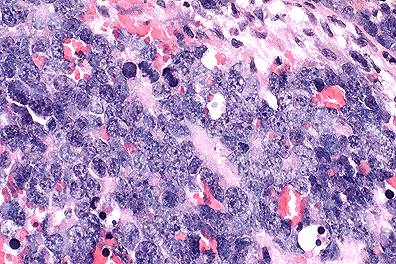

Retinoblastoma cells in a mouse. (40X, HE, 103K)

Contributor's Comments: The ocular mass, which in most sections is confined to the globe, is composed of pleomorphic, poorly differentiated, neoplastic retinoblasts arranged in cords and sheets. The cells are polygonal with scant cytoplasm and large "open-faced" basophilic nuclei with prominent nucleoli. There are numerous normal and bizarre mitotic figures and large foci of necrosis within the body of the mass.

Multinucleate cells are frequent and randomly distributed throughout the mass; some of these are degenerate. In some sections, extension of neoplastic cells into the optic nerve can be seen and in other sections, the degenerate lens is seen.

AFIP Diagnosis: Eye: Primitive neuroectodermal tumor, FVB line 19 transgenic mouse, rodent.

Conference Note: The retina is formed from neuroectodermal cells which line the floor of the primitive forebrain. Retinoblastomas arise from the neuroectoderm of the optic cup. In this case, the tumor appears to originate at the optic cup and expands into the vitreous chamber, elevating and detaching the retina. The tumor also invades the optic nerve in some sections, a common finding in retinoblastomas. This case was reviewed by the staff of the Department of Ophthalmic Pathology, AFIP. They believe that this tumor is neuroectodermal, but lacks sufficient differentiation to be definitively classified as a retinoblastoma. Thus, a diagnosis of primitive neuroectodermal tumor is favored.

The Rb gene is a tumor suppressor gene. Tumor suppressor gene protein down regulates cell proliferation. In humans, 60% of retinoblastomas occur sporadically, and the other 40% are familial. This ratio of occurrence has been explained by the "two hit" hypothesis. In familial cases of retinoblastoma, an individual is born with a mutant Rb gene on a single allele, the first hit. The second hit is a mutation of the second allele of a retinal cell that carries the original mutant allele. In sporadic cases, mutation of both alleles must occur in a single retinal cell. In either case, the retinal cell loses both copies of the Rb gene and unregulated proliferation ensues. As the contributor notes, FVB 16 mice carry the human papilloma virus 19 E6 and E7 genes. The gene products of E6 and E7 interact with the Rb gene product, interfering with the regulatory mechanism of the Rb gene product. Although the mechanism of inactivation is different between naturally occurring cases in humans and the transgenic mouse model, the end result is the same; loss of down regulation by Rb gene product and tumor formation.